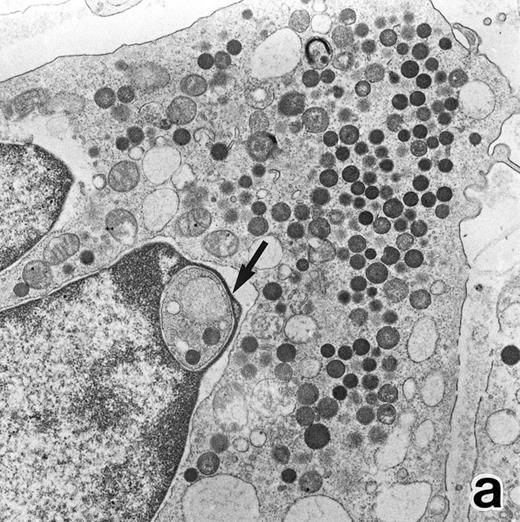

(a) A PMN in patient no. 1 after 1 week of ATRA treatment. Lobulated nuclei with a nuclear bleb (arrow) is seen. rERs are still dilated. Note that the primary granules have become normal in both size and shape and that neither Auer rods nor irregularly shaped inclusion bodies are seen in this cell. (Original magnification × 16,900.) (b) Higher magnification of the cytoplasm of another cell in patient no. 1, showing a structure in which a spherical primary granule (arrow) and an Auer rod are coupled. (Original magnification × 40,000.)

Common morphological changes of bone marrow leukemia cells were observed during ATRA treatment. After 1 week of ATRA treatment, leukemic cells showed heterochromatin condensation and nuclear lobulation (Figs 3 and 4). Although the lobulated nuclei of some cells resembled those of PMNs, these nuclei were irregular in shape and nucleoli were occasionally present. The lobulated nuclei often had nuclear blebs (Fig 3a) or were connected by thin nuclear material (Fig 4a), called filamentous connections,13 that consisted of heterochromatin delimited by the nuclear membrane. In addition to these changes, the irregularly shaped primary granules became morphologically normal. This was most evident in patient no. 1, in whom the majority of both Auer rods and irregularly shaped inclusions, as shown in Fig 2, dramatically vanished and the remaining primary granules appeared normal, being spherical in shape and relatively homogeneous in size (Fig 3a), although abnormal primary granules and/or Auer rods were infrequently observed in some cells. Rarely, a structure composed of an Auer rod coupled with a primary granule was found, appearing as though the seemingly normal primary granule had emerged from the Auer rod (Fig 3b). Type I primary granules still predominated in all patients, but type II primary granules with a nucleoid structure were rarely observed in patients no. 1 and 2. Some maturing neutrophils with abnormally shaped lobulated nuclei in patient no. 2 possessed unusual, possibly immature, primary granules containing central electron-dense material (Fig 4a and b), indicating asynchronous maturation of nuclei and cytoplasmic granules.